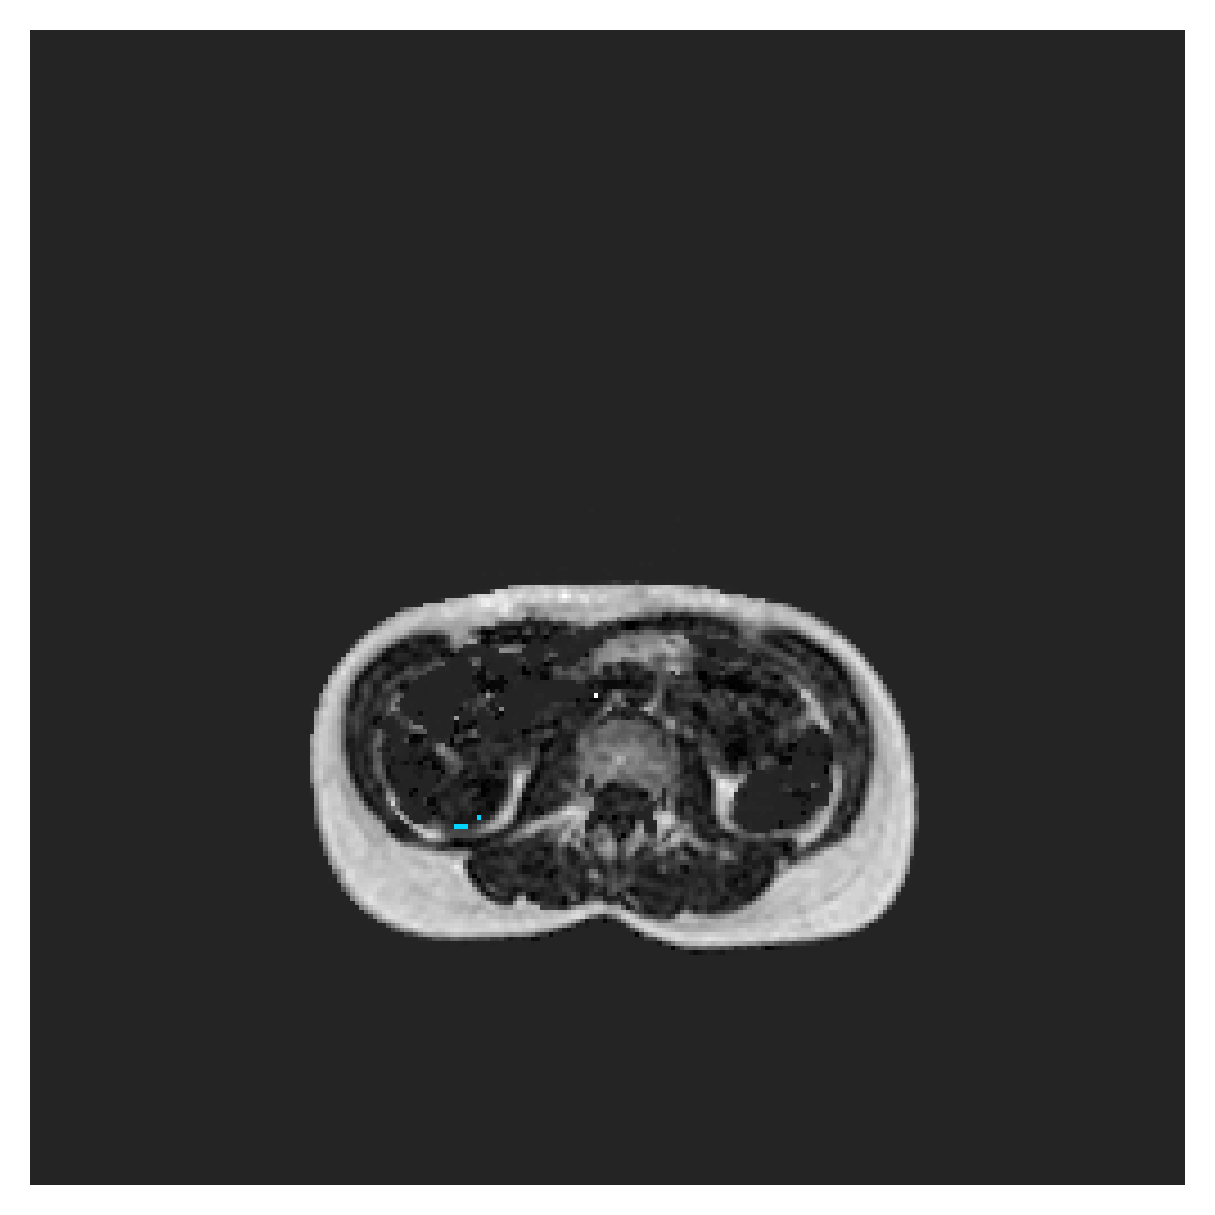

POEM

The Prospective investigation of Obesity, ENergy production and Metabolism (POEM) is a local (not currently publicly available; PI: L. Lind, see [22] for details) cohort of whole-body fat/water separated MR images. Full annotations of the liver, kidneys, bladder, pancreas and spleen are available for 50 subjects, providing a challenging segmentation dataset with heavily imbalanced classes of varying shapes. The resolution of the data is anisotropic, with reconstructed voxel size of in left-right, anterior-posterior and foot-head directions, respectively. For additional technical details regarding the acquisition and specifications of the images see [22].

The images contain two channels, one for water and one for fat content. For training, we normalize the volumes (per channel) and use 2D slices in the coronal plane, sized . The weak annotations are created synthetically, following the same procedure as described for the ACDC dataset.